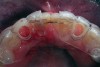

A 19-year-old non-smoking female presented for tooth replacement at the maxillary right and left lateral incisors, which were congenitally missing (Figure 1). The post-orthodontic result was adequate for the placement of 3-mm one-piece small-diameter implants. The preoperative radiographs can be seen in Figure 2 and Figure 3. The pretreatment clinical view in Figure 4 and Figure 5 shows the small intertooth space present in the lateral incisor areas. One of the most challenging tasks with congenitally missing lateral incisor cases is to create an acceptable soft tissue emergence profile from a crestal profile that is flat from the mesial of the canines to the distal of the centrals (Figure 4 and Figure 5). After pretreatment planning which consisted of a complete medical and dental history, radiographic analysis, and upper and lower study models mounted by a facebow transfer technique, the fabrication of a TempStent II surgical guide was completed. Figure 6 and Figure 7 show the occlusal view of the TempStent II guide on the study cast and in the oral cavity, respectively.

Figure 6  Occlusal view, TempStent II Surgical Guide.

Figure 6

Figure 7  Intraoral occlusal view, TempStent II Surgical Guide.

Figure 7